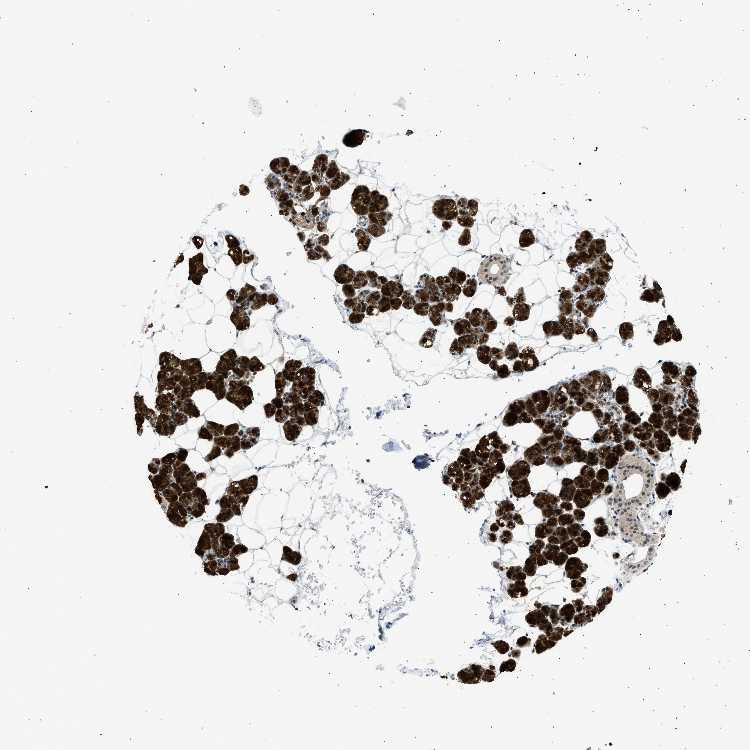

SALIVARY GLAND - Antibody stainingi

Antibody staining in the annotated cell types in the current human tissue is reported as not detected, low, medium, or high, based on conventional immunohistochemistry profiling in selected tissues. This score is based on the combination of the staining intensity and fraction of stained cells.

Each image is clickable and will lead to virtual microscopy that enables deeper exploration of all samples and also displays staining intensity scores, fraction scores and subcellular localization as well as patient and tissue information for each sample.

Antibody HPA019824Antibody CAB015201

Glandular cells Not detectedHigh